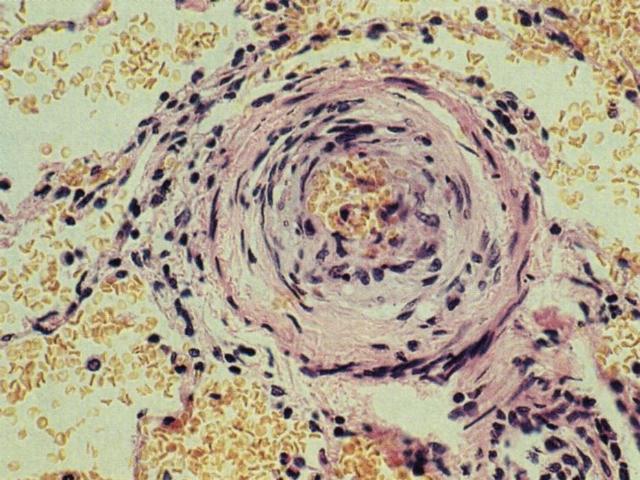

El Tromboembolismo pulmonar (TEP) es una patología frecuente del pulmón. El TEP es una secuencia de eventos que comienza con la formación de trombos en órganos a distancia conectados al pulmón por circulación venosa. Es importante mencionar que el pulmón es el único territorio capilar que recibe circulación venosa en forma aferente, por lo que cualquier trombo generado en distintos órganos tiene el riesgo potencial de afectar el capilar pulmonar. La migración del trombo al pulmón se llama embolo y de ahí el término trombo-embolismo pulmonar. La principal causa de TEP es la trombosis venosa profunda. Esta y otras causas de TEP se muestran en la figura [imagen]. Como se observa diversas causas además de la trombosis pueden ser causa de TEP como por ejemplo la embolía de líquido amniótico o la embolia grasa [imagen].. La gran mayoría de los TEP son subclínicos, son microembolías que en forma crónica pueden llegar a provocar Hipertensión Pulmonar. Sólo los TEP masivos pueden provocar sintomatología clínica [imagen]. Los cortes histológicos de esta lesión revelan un trombo organizado compuesto por capas alternadas de eritrocitos y leucocitos / fibrina [imagen]. La consecuencia de esta lesión en el pulmón será la hemorragia [imagen] y el infarto hemorrágico del pulmón.[imagen]